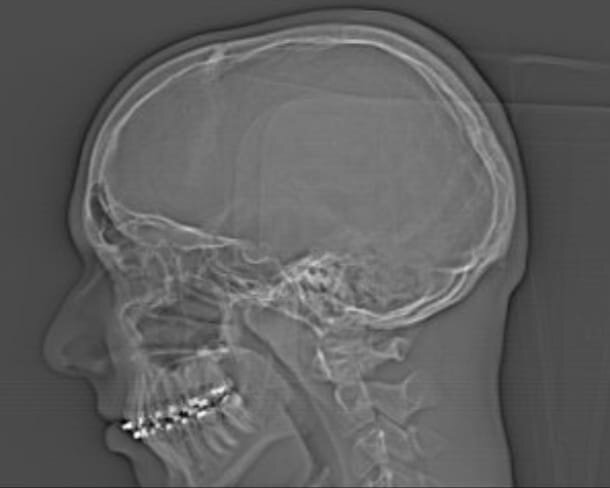

I provided pictures and CT scan. I had one non invasive nasal laser surgery which gave me 20 percent more air. My nose is crooked and my orthodontist told me to get it fixed in like 2 years because i am still growing and the face might grow not symmetrical. The septoplasty will be paid for by insurance. I mouth breathed for many years because I did not get enough oxygen through my nose.

For me the question is if I qualify for bimax or similar surgery before septoplasty. I got lack of volume in under eye area. My jawline is recessed. I got also next to my nose these curves which indicate recessed midface. On top of it I got a flat upper lip which indicates recessed maxilla. I still dont get enough air and struggle sleeping on my back. For eyebrows I have been taking caster oil with micro needling for 2 months and tried trimming them. Im also considering retionol for under eye area.

I had braces with these elastic bands which might have pulled my jaw back. I had 3 molar teeth extracted and 1 left because of "lack of space" (regret it)